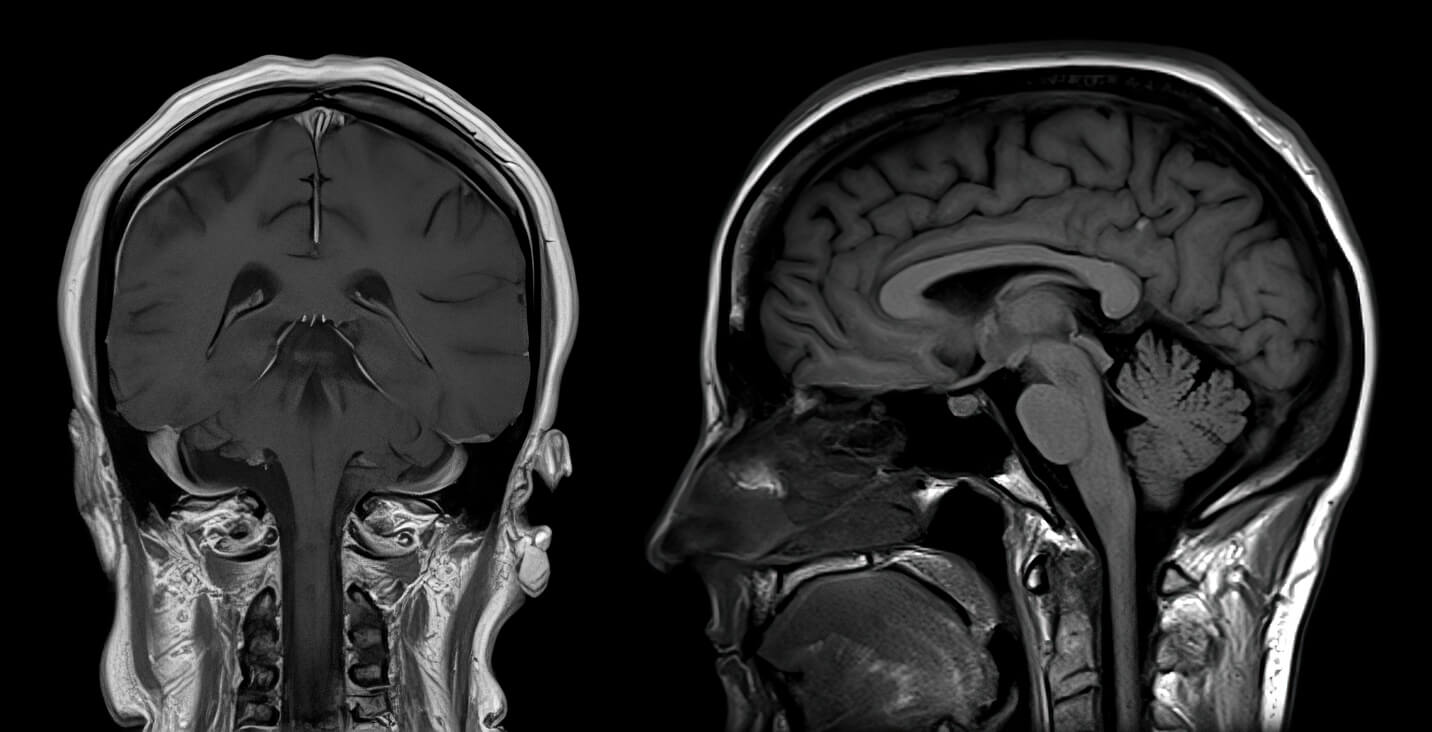

Brain Check MRI